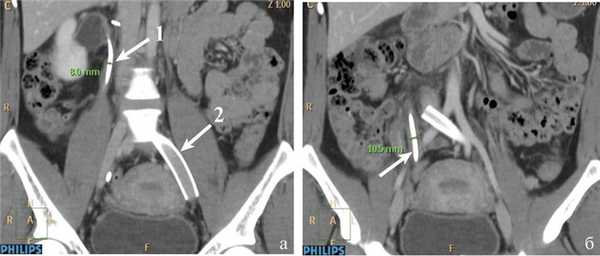

В клинике больная дообследована. В анализах крови и мочи значимых изменений не обнаружено. Помимо общеклинического обследования, выполнено трансабдоминальное и трансвагинальное ультразвуковое ангиосканирование (УЗАС), по результатам которого обнаружены расширение параметральных вен до 10 мм, маточных вен до 7 мм, правой гонадной вены до 8 мм, патологический рефлюкс крови по этим сосудам. Ультрасонографических признаков патологии подвздошных вен не выявлено. В ходе выполнения мультиспиральной компьютерной томографии (МСКТ) с контрастным усилением диагностированы правосторонняя пиелоэктазия до 50×28 мм, расширение мочеточника в средней и нижней трети до 15 мм, сужение просвета левых подвздошных вен, расширение правой гонадной вены (рис. 1). Рис. 1. Компьютерные томограммы пациентки М. а — расширение правой почечной лоханки; б — стеноз левой общей подвздошной вены (указано стрелками). Органической патологии органов малого таза, забрюшинного пространства не выявлено.

Для уточнения диагноза и определения тактики лечения выполнены ренофлебография, оварикография, тазовая флебография. По результатам флебографического исследования выявлены: сдавление правого мочеточника расширенной правой гонадной веной в верхней трети, расширение правого мочеточника в средней и нижней трети, стеноз левой наружной и общей подвздошной вен до 95% неопухолевого и нетромботического генеза, расширение левой внутренней подвздошной вены и ее притоков, депонирование контрастного вещества в варикозных венах малого таза (рис. 2). Рис. 2. Флебограммы пациентки М. а: 1 — правая гонадная вена; 2 — S-образный изгиб мочеточника в верхней трети; 3 — сдавление правого мочеточника правой гонадной веной; 4 — расширенный мочеточник в средней и нижней трети; б — стеноз общей подвздошной вены (указано стрелками). Случай расценен как синдром Мея—Тернера, тазовое венозное полнокровие, синдром правой гонадной вены. Учитывая выраженное сужение левых подвздошных вен, высокий риск развития венозных тромбоэмболических осложнений, первым этапом лечения решено выполнить эндоваскулярное стентирование левых подвздошных вен. Проведена имплантация стента Wallstent—Uni 14×60 мм. На контрольной флебографии определяется полная проходимость подвздошных вен (рис. 3). Рис. 3. Флебограмма пациентки М. Стент в левых общей и наружной подвздошных венах (указано стрелками). После стентирования проводили антикоагулянтную и дезагрегантную терапию (клексан 60 мг 2 раза в сутки под кожу живота, плавикс 75 мг/сут в течение 3 нед, затем клексан 40 мг/сут однократно). Постимплантационный период протекал без осложнений.

Учитывая выраженную диффузную кровоточивость тканей (пациентка получала низкомолекулярный гепарин в профилактической дозе), в забрюшинное пространство установлен силиконовый дренаж. Продолжительность операции составила 50 мин, кровопотеря — около 100 мл. Послеоперационный период без осложнений, дренаж удален на 1-е сутки после вмешательства. Через 2 дня после операции пациентка отметила значительное уменьшение болевого синдрома. При повторных ультразвуковых исследованиях и МСКТ на 3-й день послеоперационного периода сохранялись правосторонняя пиелоэктазия и расширение правого мочеточника, в связи с чем решено выполнить временное стентирование правого мочеточника (рис. 5). Рис. 5. Компьютерные томограммы пациентки М. после стентирования мочеточника. а: 1 — мочеточниковый стент в верхней трети; 2 — стент в правых подвздошных венах, проходимость его не нарушена; б — мочеточниковый стент в нижней трети (указано стрелками).